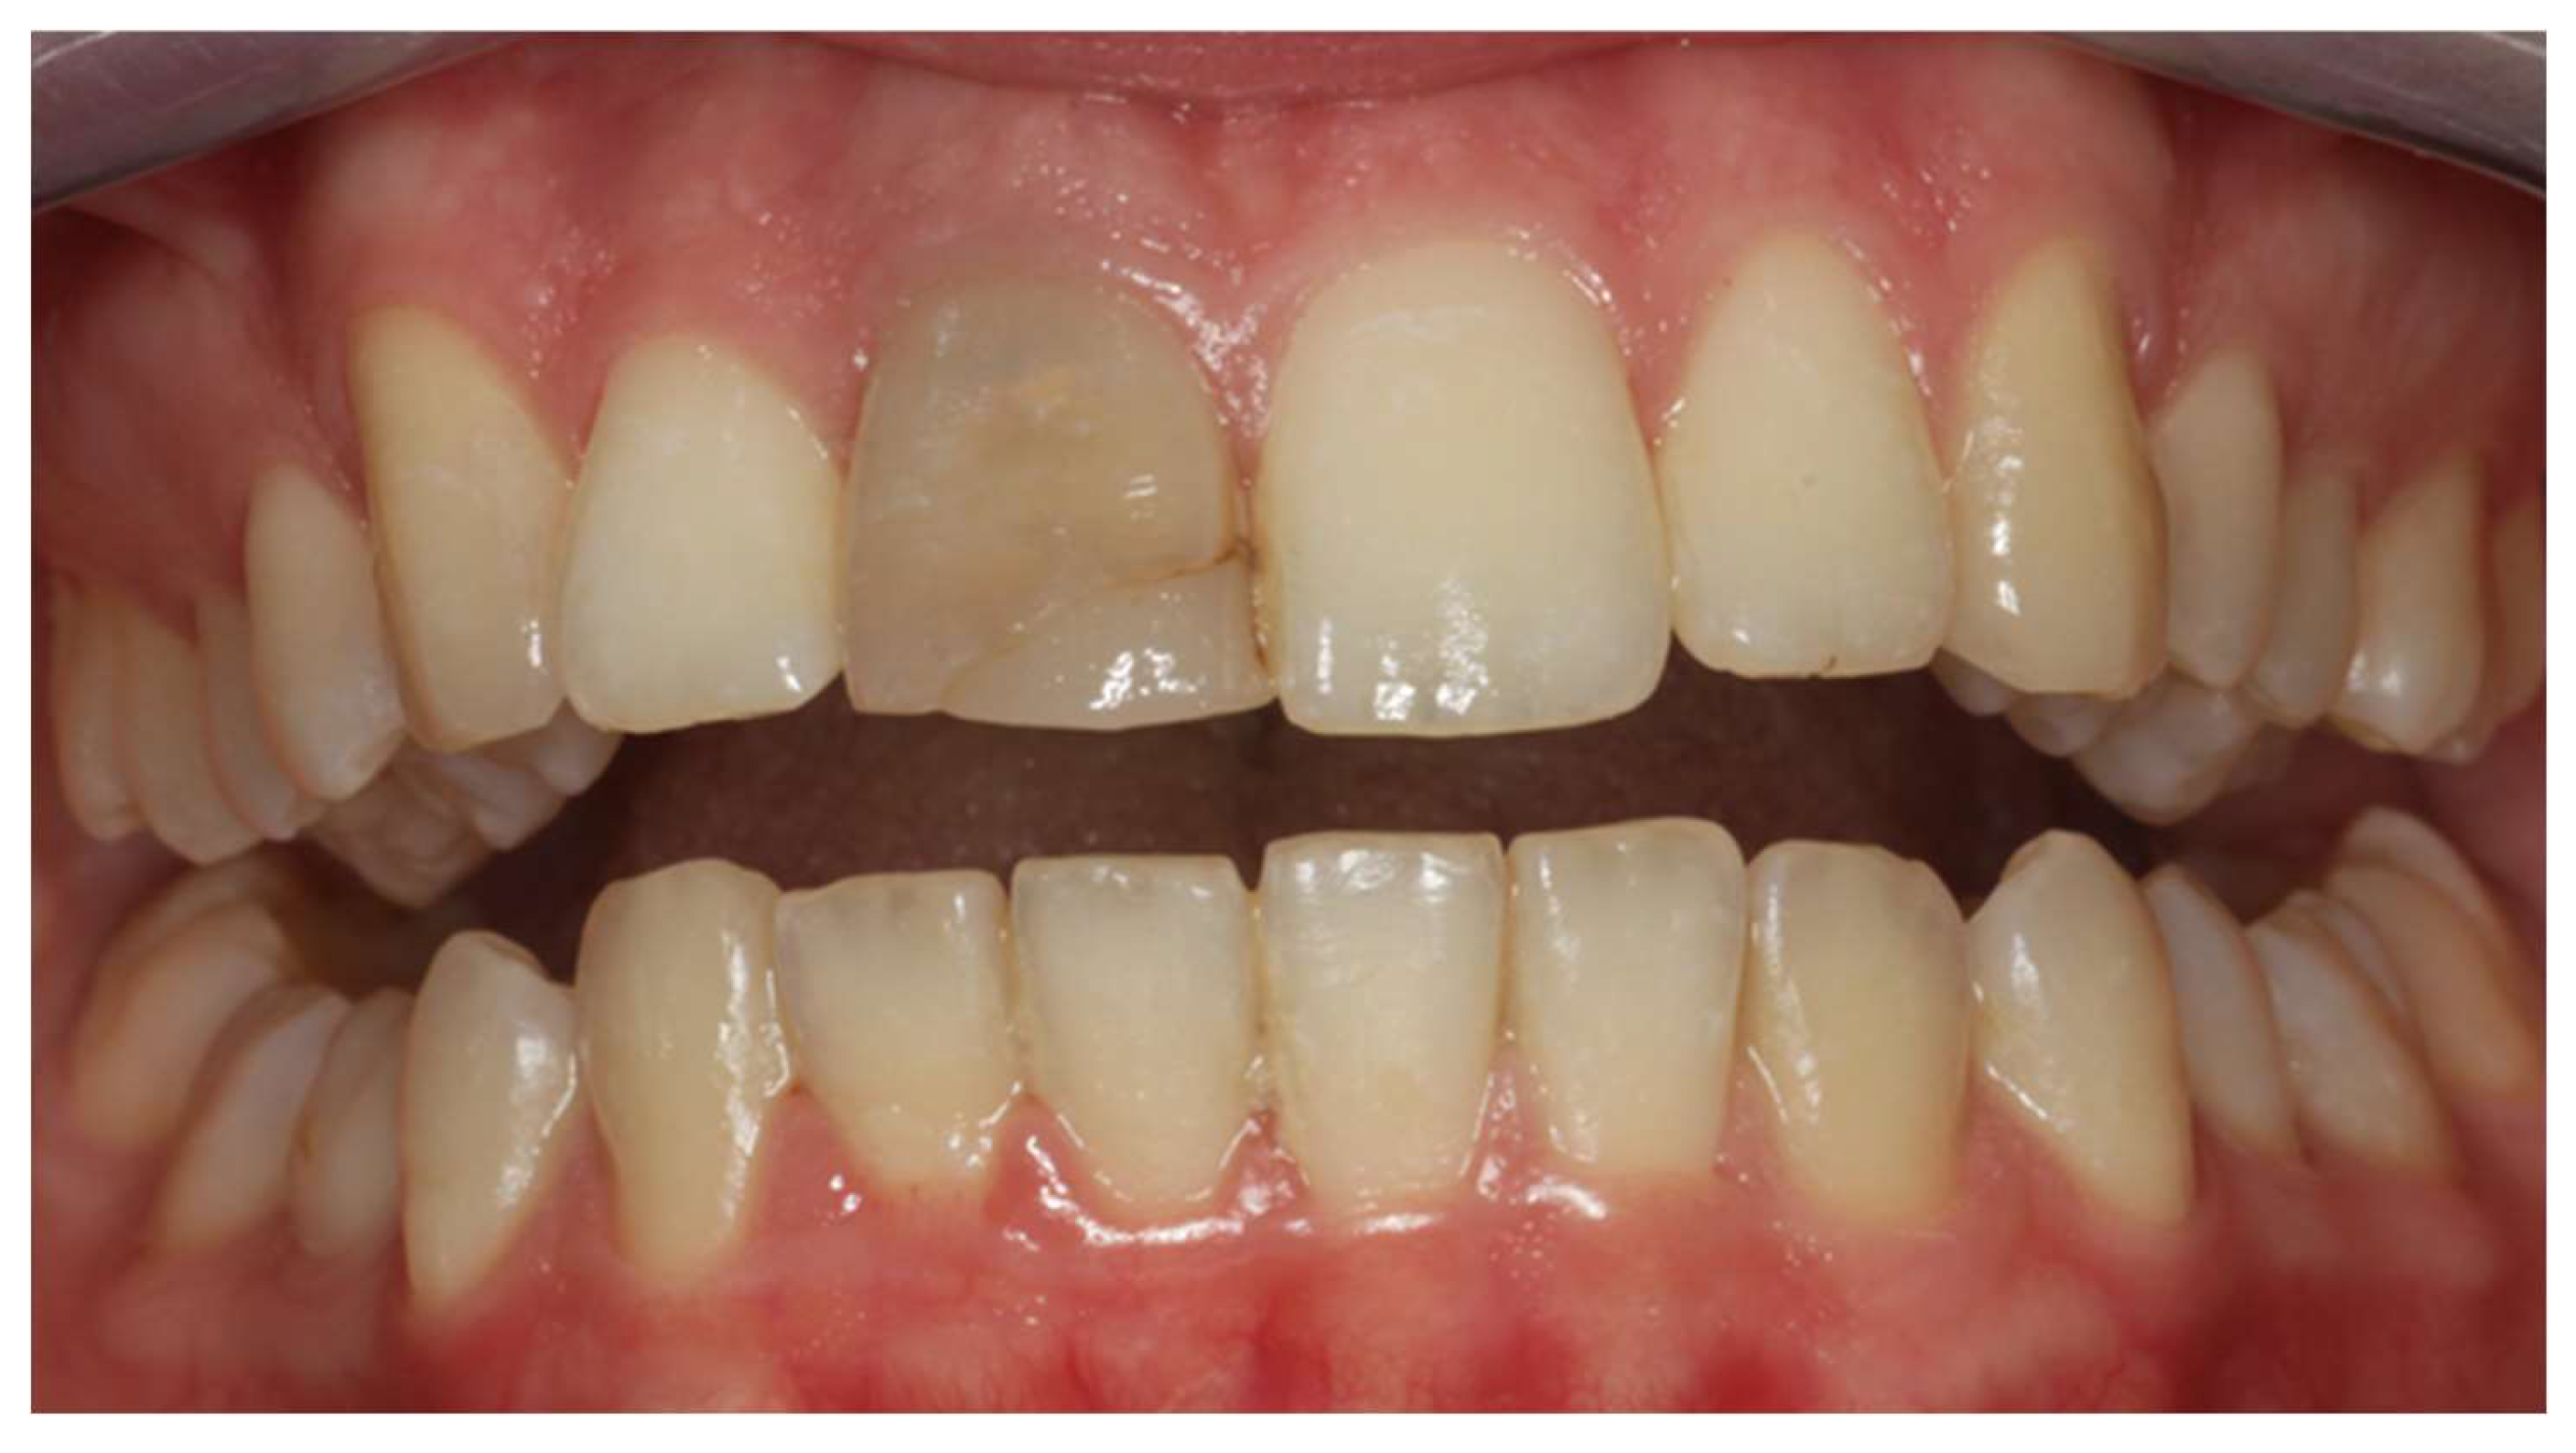

2. Clinical Case